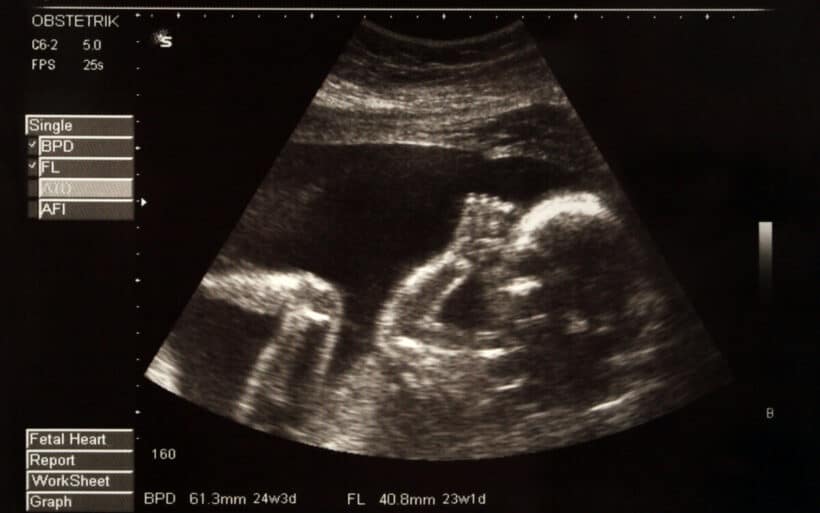

Gebeliğin son dönemindeyim. Doktor bebeğin ters durabileceğini söyledi. Bunu görüntüde nasıl fark edebilirim?

benim doktor ultrasonla gösterdiğinde bebeğin pozisyonunu direkt anlamıştım. ters durduğunda baş yukarıda popo aşağıda görünüyo zaten. bazen anne karnındaki hareketlerden de bi şeyler çıkarabilirsin ama kesin bilgiyi sadece ultrason verir. ben ilk öğrendiğimde çok şaşırmıştım çünkü kendi hislerimle hiç anlayamamıştım